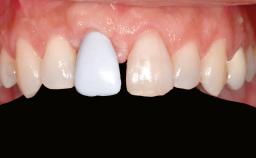

A 47-year-old woman who had suffered from aggressive periodontitis requiring a number of periodontal interventions over more than 10 years was referred by her general dental practitioner and periodontologist for bone augmentation and implant therapy. Her failing dentition had already been scheduled for extraction. The patient expressed a desire for implant-supported fixed restorations and esthetic improvement of her lower face. She had agreed to consult with a maxillofacial surgeon after the referring dentist had suggested bone augmentation. An initial examination by the maxillofacial surgeon revealed mobility of all residual teeth in a patient who was very unhappy with the function of her removable partial dentures. Due to periodontally migrated flaring teeth and loss of occlusal support, the vertical dimension of occlusion was dramatically reduced. The patient was displeased with her lower face because of deepened nasolabial, commissural, and supramental folds.

Prosthesis Type FDP

Patient's Esthetic Expectations Low Medium High

Lip Line No exposure of papillae Exposure of papillae Full exposure of mucosa margin